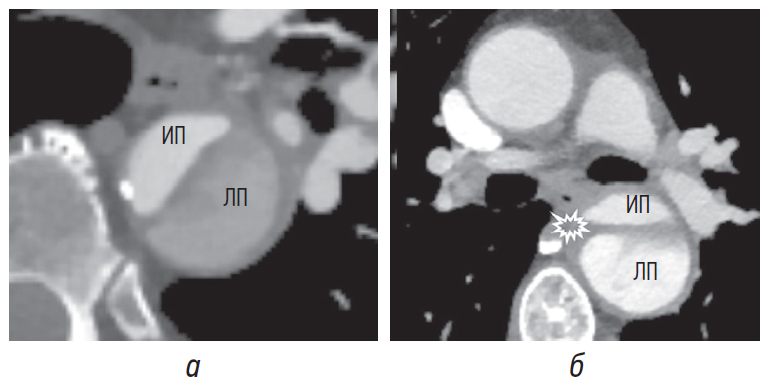

Тромбоз просвета аорты

Обычно истинный просвет в артериальную фазу сканирования начинает контрастироваться раньше ложного (рис. 12, а) [6]. Поскольку в ложном просвете кровоток чаще замедлен, в нем могут наблюдаться потоковые артефакты (рис. 12, а, б) и частичное тромбирование (рис. 12, б) [1]. В случаях острой диссекции по сравнению с хронической из-за плохого контрастирования просвета бывает сложно отличить эти потоковые артефакты от тромба ложного просвета [3, 7]. Следует отметить, что при сканировании в артериальную фазу контрастирования ложный просвет может не усиливаться, что создаст имитацию тромбирования. Во избежание неправильной диагностики тромбоза просветов мы рекомендуем дополнительно выполнять сканирование в венозную фазу.

Рис. 12. Потоковые артефакты в ложном просвете (а, б) с пристеночными тромботическими массами (б). ИП — истинный просвет, ЛП — ложный просвет

Необходимо определить наличие тромботических масс в истинном и ложном просветах, поскольку проходимость именно ложного просвета аорты оказывает существенное влияние на долгосрочный клинический успех и выживаемость пациента. Сохранение проходимости ложного просвета (рис. 13, а) неблагоприятно сказывается на долгосрочной выживаемости пациента, при этом отмечается положительный эффект полностью тромбированного ложного просвета (рис. 13, б) в хроническую стадию [6, 10].

Рис. 13. Ложный просвет с сохранением проходимости и частичным тромбированием (а), полностью тромбированный (б). ИП — истинный просвет, ЛП — ложный просвет

Внутрипросветный тромб можно расценивать как информативный маркер ложного просвета, поскольку там он встречается чаще по сравнению с истинным просветом. Необходимо помнить о том, что у пациентов с исходно существовавшей аневризмой тромб может присутствовать и в истинном просвете (рис. 14) [8].

Рис. 14. Пристеночный тромбоз истинного просвета (стрелка) при исходно существовавшей аневризме брюшного отдела аорты. В данном случае на то, что это действительно истинный просвет, указывает кальциноз внешней стенки и интимомедиального лоскута, обращенного в его просвет. ИП — истинный просвет, ЛП — ложный просвет

Тромбоз ложного просвета значительно чаще встречается при хронической диссекции, чем при острой. Тромбообразование в ложном просвете в случаях хронической диссекции связано с его псевдоаневризматическим расширением, низкой скоростью кровотока и атероматозными изменениями неоинтимы [7, 8].